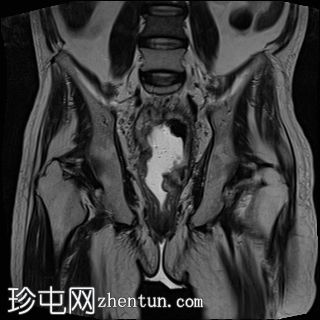

轴位

T1加权像

直肠下三分之一处可见一段弥漫性不规则肠壁增厚,伴浆膜外延伸,在右前外侧壁形成“C”形肿块,增强后呈不均匀强化,中央可见坏死。

左侧外侧壁和后壁可见大片缺损,内含气体和粪便,被不规则增厚的肠壁包裹。该缺损在T1加权像上呈低信号,在T2加权像上呈高信号,并伴有明显的扩散受限。

可见肠系膜脂肪间隙条索状改变和水肿。